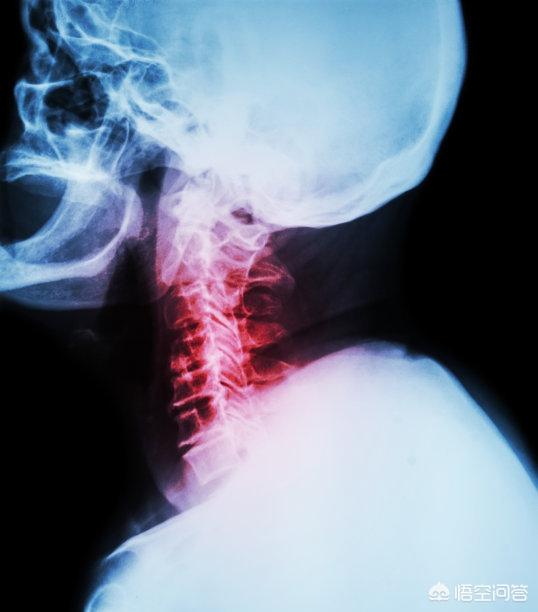

頚椎症は、退行性の病的変化に基づく疾患である。頚椎症は退行性病変に基づく疾患であり、主に頚椎の長時間の歪み、骨軟化症、椎間板の脱落や靭帯の肥厚などにより、頚髄、神経根、椎骨動脈などが圧迫され、一連の機能障害が発生する臨床症候群である。

頚椎症の種類と症状から、主に頚椎症、神経根頚椎症、脊髄頚椎症、椎骨動脈頚椎症、交感神経頚椎症、食道圧迫頚椎症がある。

頚椎症は、局所性頚椎症、根性頚椎症、脊髄性頚椎症、椎骨動脈性頚椎症、交感神経性頚椎症、混合性頚椎症に分類される複雑な病状である。

頚椎症は、頚椎の椎体と椎間板が関与する進行性の変性疾患プロセスである。その結果、頸椎中央部の脊柱管が狭窄し(狭窄)、頸髄が圧迫され、脊髄機能障害症候群(すなわち、脊椎症性頸椎症)が発症する。脊椎症性頸椎症は、症候性頸椎症患者の5~10%にみられる。頚椎症に関連するその他の臨床症状には、頚部痛や頚部神経根症がある。

脊椎症性頚椎症は、55歳以上の成人における脊髄病変の最も一般的な原因であり、進行性の身体障害と生活の質の低下につながる。